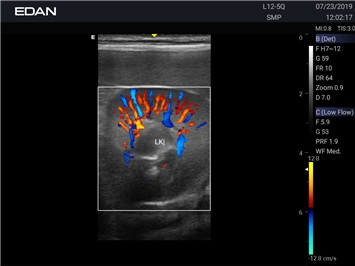

Энергетический допплер:

Да

Цветовой допплер: